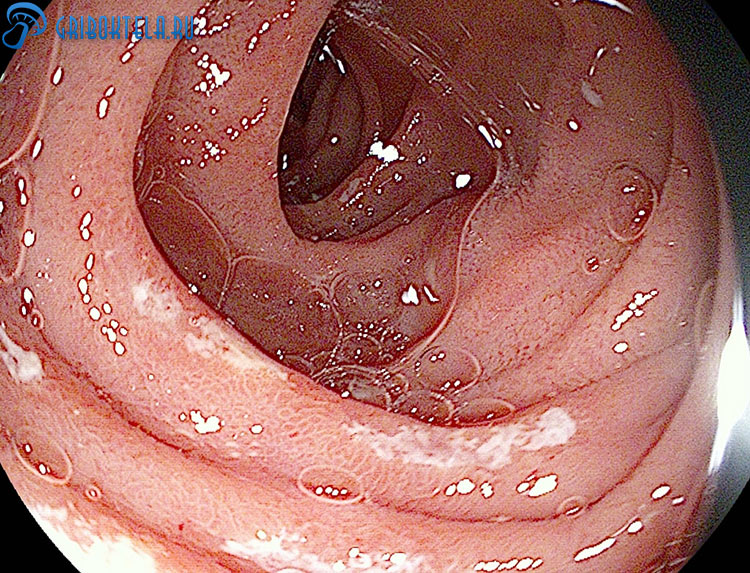

При поражении ротовой полости определяется воспаление слизистой, белый налет, легко снимающийся шпателем или марлевым тампоном и боль во время приема пищи.